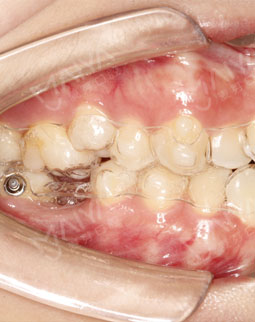

拿到牙套了,其实还有点怀疑,就这两个塑料的东西,真的可以让我的牙齿矫正吗,何况我还有个缺牙的间隙,看了墙上很多顾客和医生的合影还一墙的牙套盒,20多副的有,3、4十副的也有,很多人选择应该没错的!医生说根据个人情况有不一样的方案,我的是42副,隔断时间换一副,牙齿变齐了牙套也要跟着变化的!医生还给我演示了3D的动画,居然这么的高科技!另外医生提醒我注意刷牙卫生,还有一些注意事项,原来牙套戴在牙上是有感觉的,还真的看不出来,隐形的贵也有道理的哈O(∩_∩)O

经朋友介绍来矫正,医生说了一堆安慰我年龄不是问题,服务态度好好哦~另外说牙齿非常不整齐,右下有个磨牙缺失不能种,为了我的工作考虑,采取了隐形正畸技术,拔了智齿,然后排齐牙齿,上图,这就是露牙后的效果,总感觉哪里怪怪的~~